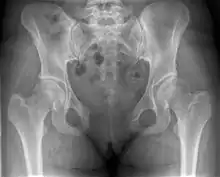

Pubic symphysis diastasis

| Post traumatic pubic symphysis diastasis | |

This abnormally wide gap can be diagnosed by radiologic studies such as X-ray, Ultrasound, MRI, CT scan or bone scan. While X-Ray is the gold standard to identify a separation of the pubic symphysis, a decision must be made in regard to which imaging modality to utilize that is patient and case-specific.[3]

An X-ray film obtained in the AP view of the pelvic inlet and outlet will show a marked gap between the pubic bones.[3] A normal pelvis will show a gap that is 4–5 mm. However in pregnancy the hormonal influences cause relaxation of the connecting ligaments and the bones separate up to 9 mm. A gap measuring greater than 10 mm indicates a pathological process.[3]

In addition, a view in the "flamingo stance" can be obtained to demonstrate the instability of the joint. This position consists of the patient standing with weight on one leg and the other bent.[6] A vertical displacement of more than 1 cm is an indicator of symphysis pubis instability.[7] A displacement of more than 2 cm usually indicates involvement of the sacroiliac joints.[3]